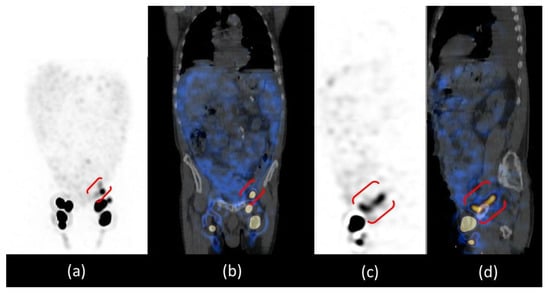

The patient was positioned supine and a dynamic anterior image of the pelvic region was acquired with a rate of 1 frame per min for 20 min that showed only the left inguinal lymph node, revealing delayed and asymmetric lymphatic drainage from lower limbs. After, anterior whole-body images were acquired at 30 and 60 min and after a high-fat meal at 2 and 3 h after administration (Figure 3). Images at 30 and 60 min confirmed the asymmetric lymphatic drainage with delayed visualization of the right inguinal lymph node (Figure 3a,b). Delayed acquisitions after a high-fat meal, showed diffuse pathological abdominal accumulation of 99mTc-labelled human serum albumin nanocolloids; furthermore, a radioactivity spot was visualized in the left iliac region where all internal iliac lymph nodes should have been removed by surgery (Figure 3c,d).

Anterior whole-body lymphoscintigraphy with 99mTc-labelled human serum albumin nanocolloids performed at the 30th minute (a) and at the 1st hour (b) after administration showed delayed and asymmetric lymphatic drainage of lower limbs. The anterior scans performed after a high-fat meal at the 2nd (c) and 3rd hours (d) showed bilateral inguinal lymph nodes, one focal spot of radiotracer uptake in the left iliac region (red arrows) and diffuse smooth abnormal abdominal radiotracer uptake (green arrows). R = right side; L = left side.

Abdominal SPECT/CT images confirmed the radioactive spot in the left iliac region and the diffuse abnormal accumulation of radiotracer in the peritoneum more intense in the left iliac fossa; the CT co-registration images showed that there was no internal iliac lymph node in that site but a dilatation of the lymphatic pathway at the site of surgical interruption, surrounded by a greater intensity of radioactivity in the ascitic effusion. The cause of chylous ascites was then identified as a consequence of the exudation of chyle through the lymphatic dilatation into the peritoneal cavity (Figure 4).

SPET/CT whole body lymphoscintigraphy: MIP (a), coronal fused image (b), sagittal SPET (c) and fused images (d). All images confirmed the presence of inguinal lymph nodes and the focal spot of radiotracer uptake in the left iliac region, which in sagittal images is better evidenced as a “whisker” due to the dilatation of the lymphatic pathway at the site of the surgical interruption (red brackets).

Furthermore, thorax SPECT/CT did not show radioactivity distribution in the left pleural effusion excluding the presence also of chylothorax and demonstrating its reactive aetiology of it (Figure 5).

SPET/CT whole body lymphoscintigraphy. MIP image (a) did not show any radiotracer uptake in the left pleural effusion visible on CT coronal image (b), excluding the presence of chylothorax (green arrow).

In our patient, lymphoscintigraphy was used to assess the presence of lymphatic changes after the surgery that involved lymphadenectomy of the iliac lymph nodes. Delayed lymphatic drainage in the right lower limb was found; in subsequent acquisitions, the images showed the presence of radioactivity in the abdominal area confirming the presence of CA and a spot in the left iliac region, which in the two-dimensional planar images could be attributable to an iliac lymph node.

For the study of lymphatic vessels, lympho-SPECT/CT moved from an ancillary role to being fundamental due to the high accuracy in detecting even minor lesions and the possibility of correlating them anatomically. Our patient is an exemplary case because lympho-SPECT/CT was decisive in characterizing the spot in the iliac area not as a lymph node but as a lymphatic dilatation and in describing the proximal greater peritoneal accumulation of radioactivity.

Images provided by lympho-SPECT/CT then allowed us to identify the CA aetiology in the exudation of chyle through the lymphatic dilatation identified, which is one of the three possible causes of postsurgical CA [1].

Another significant piece of information provided by thorax lympho-SPECT/CT is the absence of radioactivity at the site of the pleural effusion; this allowed us to identify the reactive nature of the effusion, excluding the presence of damage to the connecting lymphatic vessels [15].